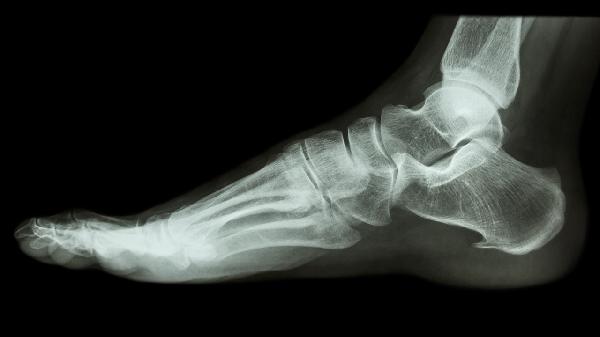

根据影像学愈合情况分阶段增加负重。初期借助拐杖部分负重行走,逐步过渡到健侧拐杖辅助。足跟先着地练习正确步态,6-8周后尝试完全负重,骨质疏松患者需延长过渡期。

踝关节骨折的症状主要包括疼痛、肿胀、淤血、活动受限和关节变形。 踝关节骨折后,疼痛是最常见的症状,通常集中在踝关...

跖骨骨折后遗症主要包括慢性疼痛、关节僵硬、足弓塌陷、创伤性关节炎等。多数患者通过规范治疗可避免严重后遗症,但恢复...